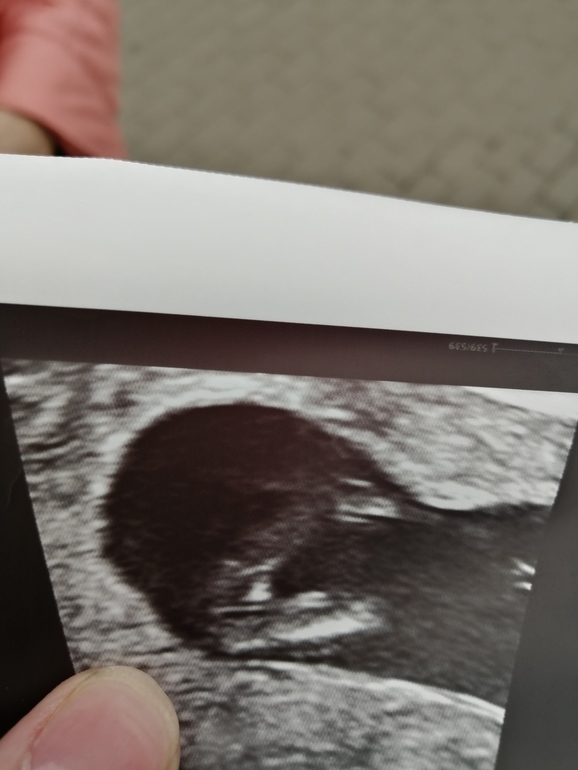

вот другой ракурс